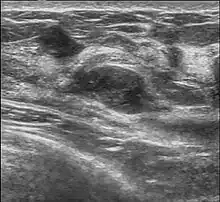

L'adénofibrome peut être perçu par la femme elle-même par la palpation des seins (perception d'une petite boule au niveau du sein, unique et indolore) ou lors d'une consultation chez sa gynécologue mais l'examen clinique, l'exploration radiologique par la mammographie et l'échographie permettent de confirmer le diagnostic ; dans certains cas, l'analyse d'un prélèvement par cytoponction (prélèvement d'un échantillon de la tumeur par une ponction à l'aide d'une aiguille spécifique) ou, plus récemment, par microbiopsie, est nécessaire pour s'assurer de la nature bénigne de la tumeur.